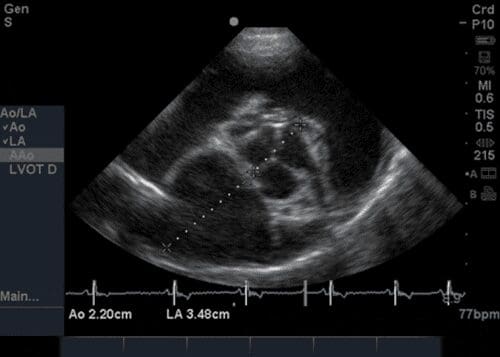

LA:Ao (Left atrium:aortic root ratio)

Right parasternal short axis view at the level of left atrium and aorta (‘Mercedes Benz’)

Measurement on frozen B-mode image

Measurement taken during diastole (just before QRS on ECG)

Measurements taken: LA Diam + Ao Diam (machine will calculate LA:Ao for you)

Lines should be drawn through middle of aortic valve leaflets and continued through left atrium in a straight line

Normal value – <1.5 in normal dog

Increased value in left atrial enlargement (disease like Mitral regurgitation)